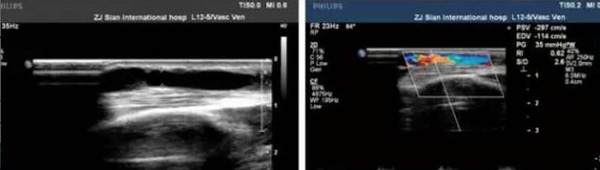

术前

术后

患者为通海县一名维持性血液透析患者,自体动静脉内瘘术后一年,近期透析时内瘘血管血流量明显不足(<200ml/min),故转诊我院肾内科。经CT血管造影术(CTA)检查发现左上肢动静脉内瘘血管头静脉段重度狭窄。术前经副主任孙阳及科室血管通路小组医护团队评估讨论,积极与B超室周宏伟主任沟通,于6月20日在B超引导下顺利进行了“内瘘血管狭窄球囊扩张成型术(PTA)”。该手术由周宏伟主任负责B超引导,肾内科卢永新主治医师负责操作,手术耗时一小时,内瘘血管狭窄段在球囊扩张下逐渐复张,术后B超评估显示狭窄段血管扩张良好,查体内瘘血管杂音及震颤明显增强,术后第二天使用内瘘血管行血透治疗,血流量达230ml/min以上,使用效果满意。